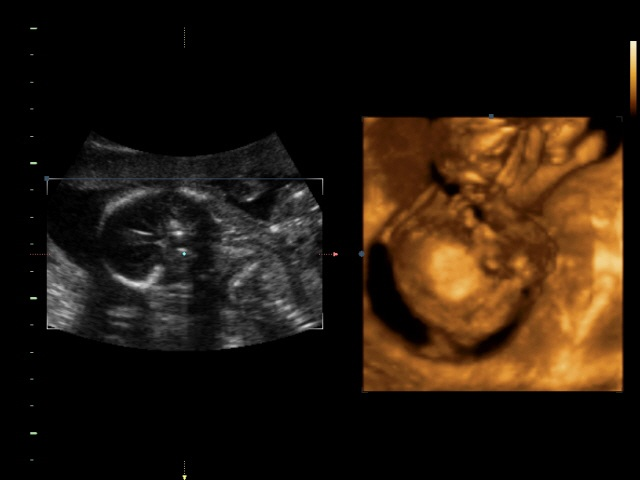

Пол малышаСходили мы на УЗИ вчера! Ходили с мамой и сыном, мужа в городе еще нет, но для него все записано на диск)) Итак, самое главное что все у нас хорошо, по мес 18 недель 4 дня(вчера ходили) по узи 19 недель 4 дня, перегнал почему то))) Малыш наш тихоня еще тот, я его почти не чувствую, спит постоянно, вот и на узи пришли, а он попой к нам повернулся, ручками закрылся, ножки поджал и все. Нииичего не увидишь(( я уже было расстроилась что всея, прийдется ждать следующего узи чтобы узнать пол, а ведь шла подготовленная, тортик поела сутра(начитавшись что сладкое приводиттак сказать малышей в движение))) но опытный врач все таки подлез к нашему малышу и.........барабанная дробь..................... МАЛЬЧИК!!! Мама попросила показать, тк по ее "правдивым и верным" подсчетам у меня должна была быть девочка( я ей поломала всю систему, тк до этого всем она считала и у всех сходилось, а у меня ни первый сын и второй-вместо девчонок)))-и тут на весь экран нам показали все наши достоинства, показали где и что расходится) а так как почти все узи мы смотрели в 4д сомнений у нас не было))) Весим мы 291гр, рост либо не написали либо я не нашла. Папа наш рад до безумия, как павлин распушил хвост и довольный))) Я тоже очень довольна, мне впринципе было все равно кто там живет, но как то больше хотелось сыну братика))) значит в третий раз пойдем за дочкой) даст Бог здоровье и благополучие и все будет хорошо!!!

Ну а вот собственно и сынок( младший))))